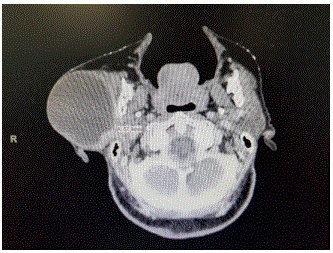

Imagem abaixo pertence a uma mulher de 82 anos, que relata ter a lesão há mais de 10 anos. Refere crescimento lento e sempre teve medo de operar, por isso nunca procurou assistência médica. Nega dor, atualmente refere apenas incomodo pelo volume local. Com base nestas informações qual a resposta correta?